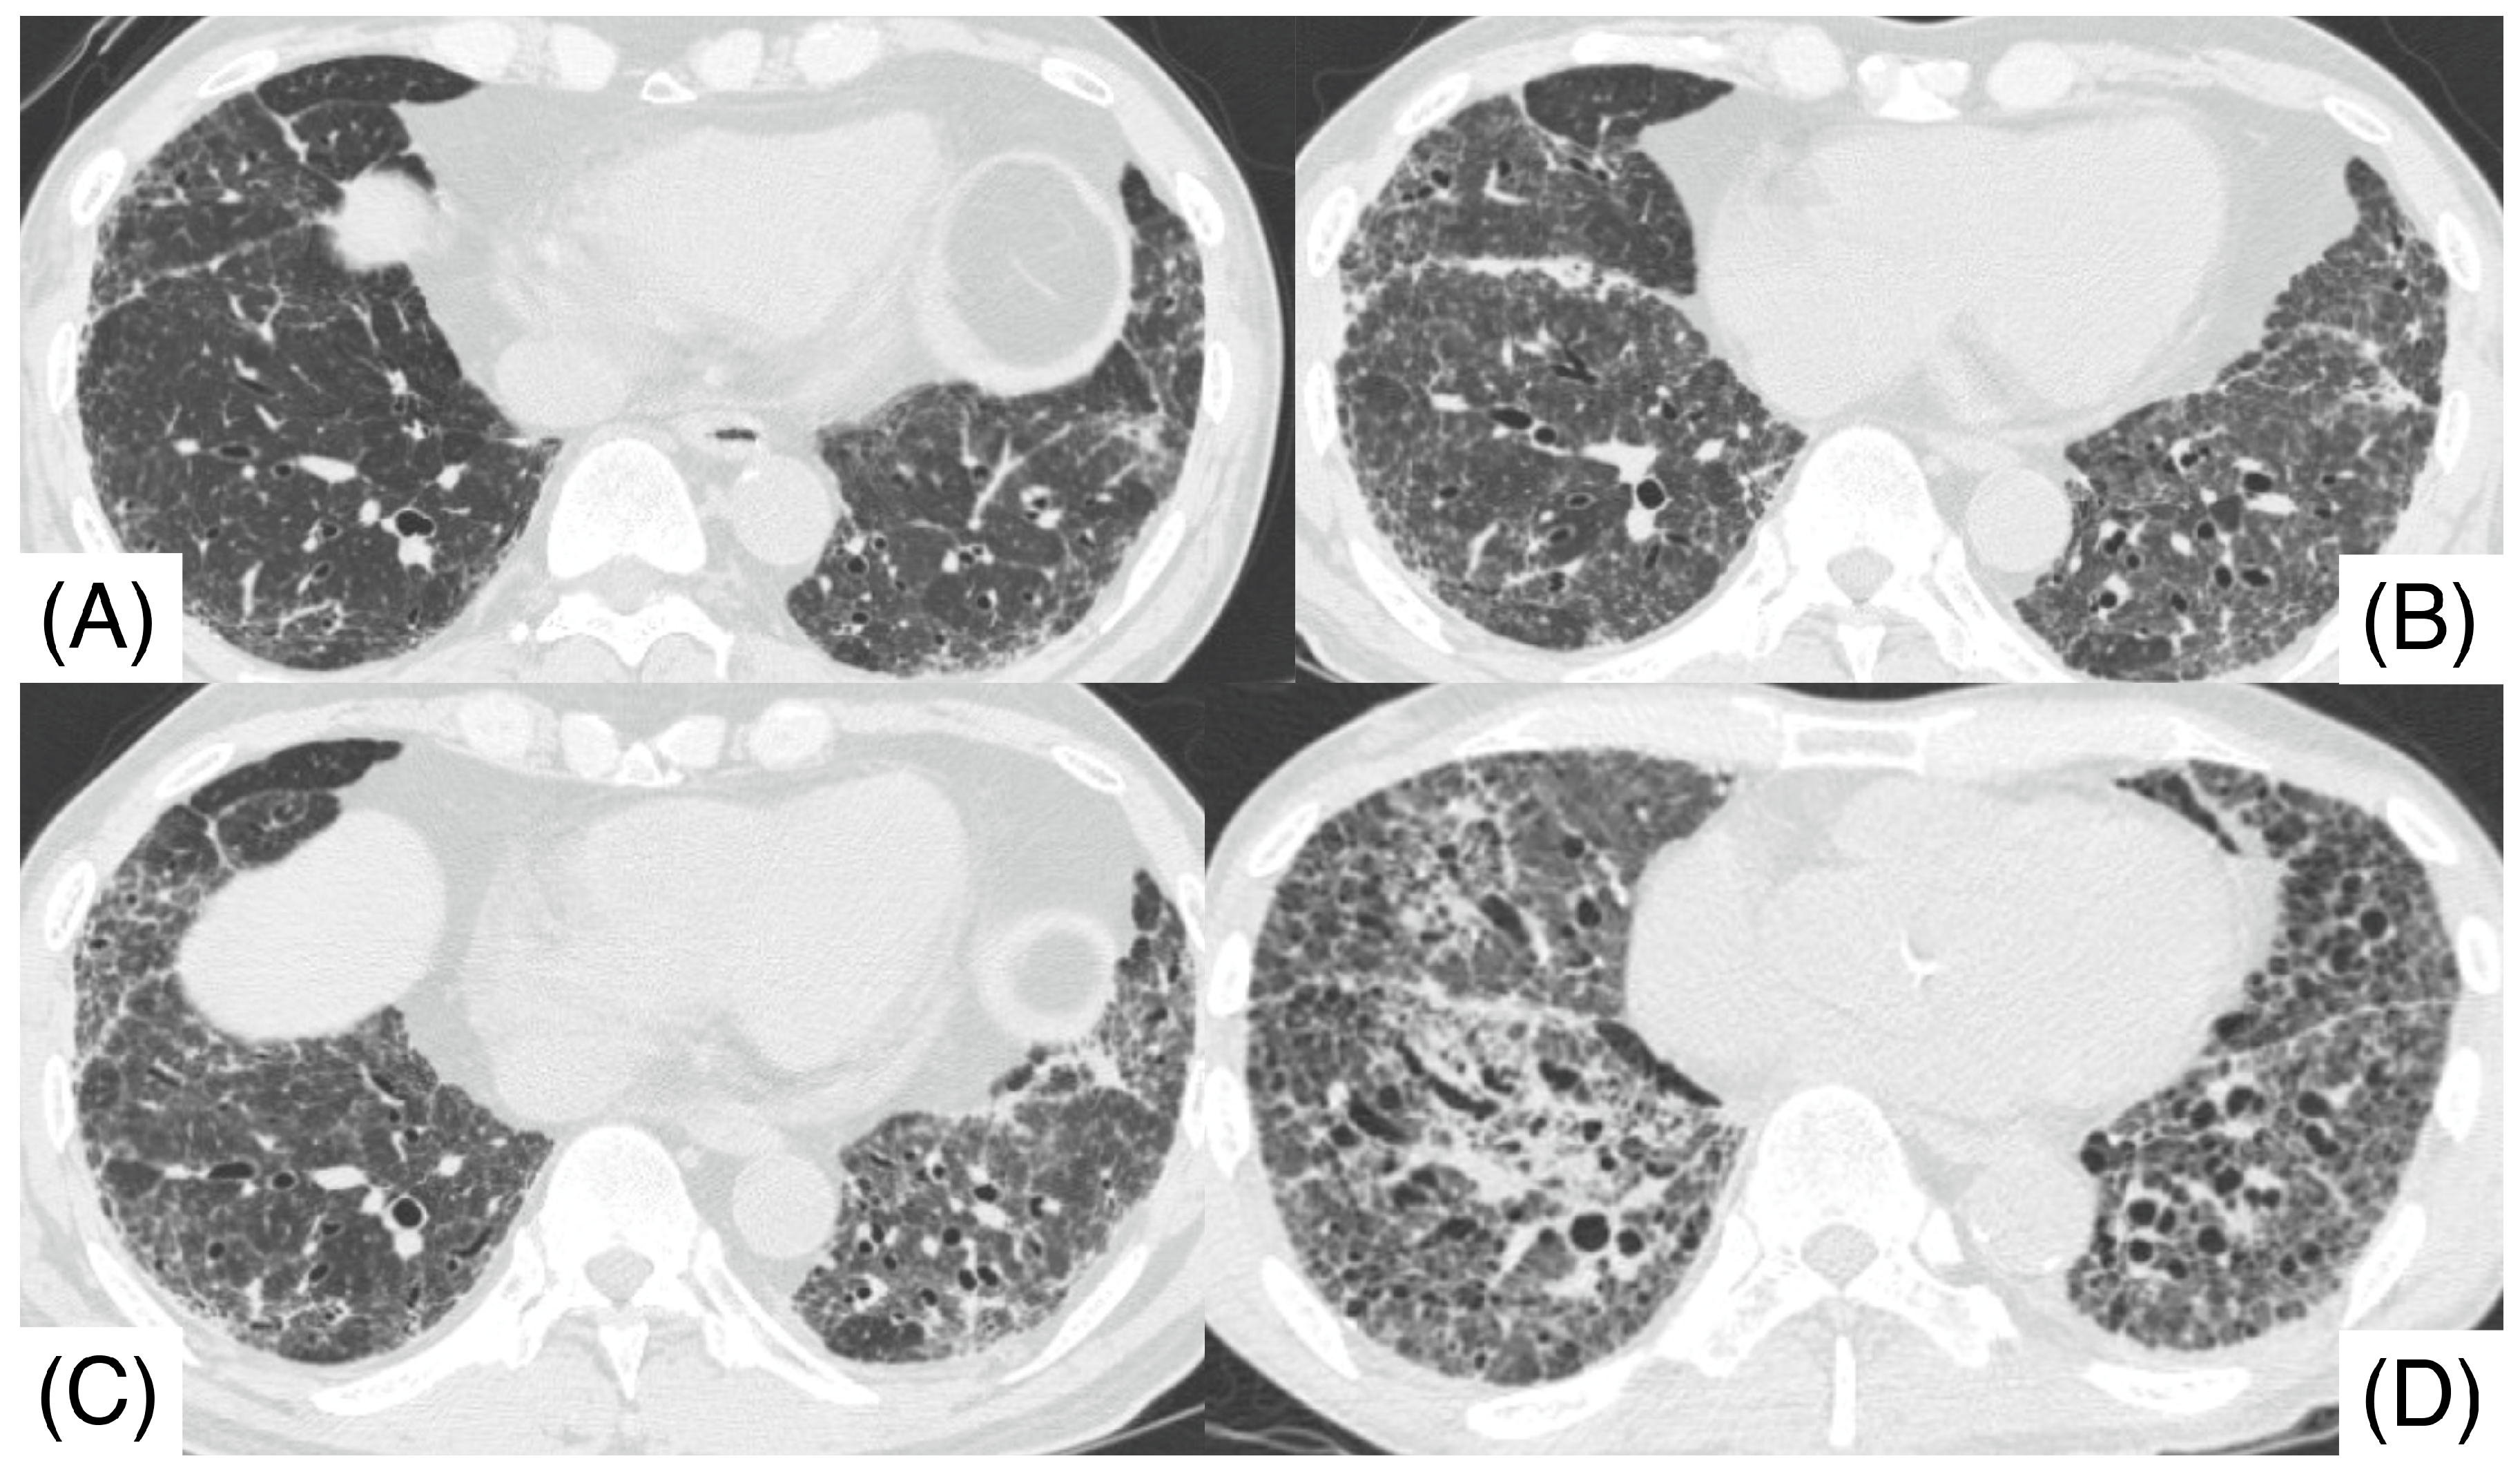

2. Case Report